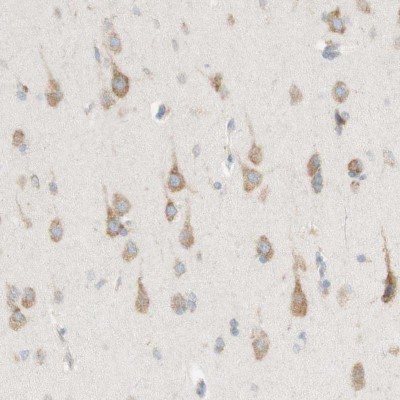

- Immunohistochemistry-Paraffin: ARMET Antibody [NBP1-90099] - Staining of human cerebral cortex shows moderate cytoplasmic positivity in neurons.